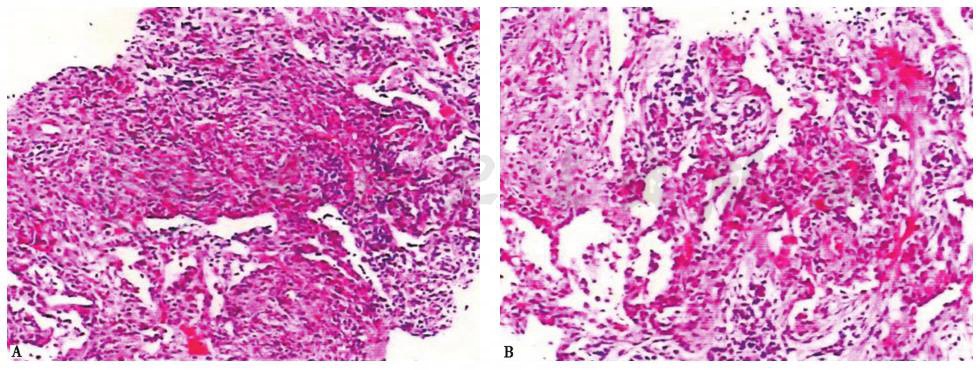

2013年1月9日病理检查结果显示,活检肺组织中见肺间质炎,淋巴细胞、浆细胞浸润,小气道和肺泡腔内局灶性息肉样纤维增生,局部淋巴滤泡形成,未见结核病变(图3)。

图3 肺组织病理表现(HE染色,200×)